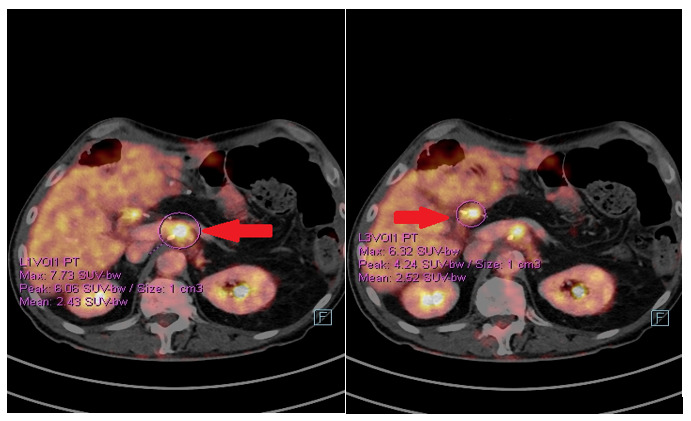

The postoperative course was uneventful and the patient started a follow-up. In January 2020, a positron emission tomography (PET)/CT scan showed the appearance of pathological tissue around the celiac trunk and in the liver hilum, which was compatible with relapse (Figure 6). Furthermore, an increase in the CA19.9 level (157 kU/l; normal range <27.0 kU/L) was detected. From 5 February 2020, the patient received rechallenge chemotherapy with nab-paclitaxel plus gemcitabine. After 4 courses of chemotherapy, he achieved a partial response manifested as a mild dimensional reduction of the solid tissue around the celiac trunk and a reduction of CA19.9 (from 447 kU/L to 115 kU/L; normal range <27.0 kU/L). However, at the end of July 2020, a rise in the CA19.9 level (from 115 kU/L to 269 kU/L) was observed, and a subsequent CT scan showed a minimal radiological progression due to an increase of the periceliac lesion (Figure 7). An ECOG PS of 0 was assessed. Thereafter, at the end of August 2020, the patient started second-line chemotherapy with liposomal irinotecan plus fluorouracil (5-FU). In the meantime, to identify a potential therapeutic target therapy, genomic profiling using next-generation DNA sequencing (NGS) and microsatellite instability analysis were performed. NGS identified the presence of KRAS G12D (exon 2) and TP53 R2495 (exon 7) mutations, while the microsatellite instability status was stable (MSS). Therefore, the possibility of targeted therapy or immunotherapy was excluded.